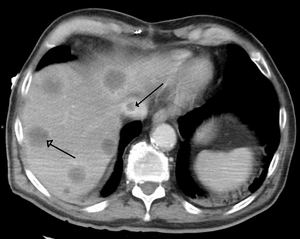

Budd–Chiari syndrome

Budd–Chiari syndrome is a very rare condition, affecting one in a million adults. The condition is caused by occlusion of the hepatic veins that drain the liver. It presents with the classical triad of abdominal pain, ascites, and liver enlargement.